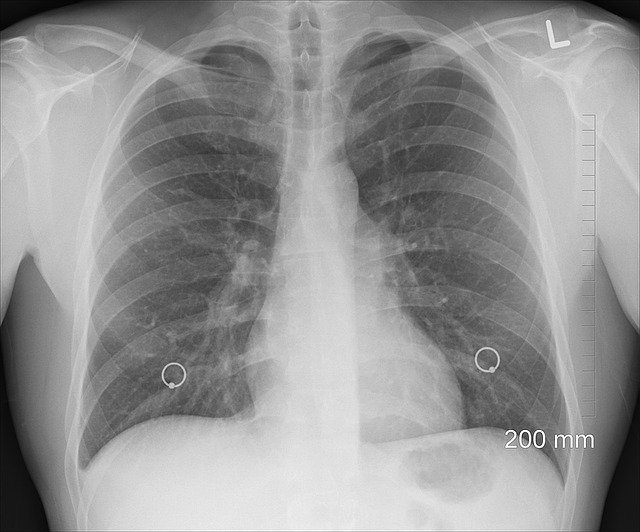

我们来科普一下这方面的常识:肺炎就是肺部发炎,影响的主要是肺泡——呼吸过程中气体交换的地方。肺炎通常会带来哪些症状、有哪些原因引起?

肺炎的症状主要是咳嗽、胸痛、发烧与呼吸困难。从轻微到严重不一,通常治疗后会好转,但痊愈后仍可感到疲倦。

某些特殊的肺炎还有特殊症状。如退伍军人菌引起的肺炎还可能有腹痛、腹泻或意识混乱;肺炎链球菌引发的肺炎,痰是锈色的;克雷伯氏肺炎菌引发的肺炎,痰是黑醋栗果冻样的血痰;霉浆菌性肺炎可能会伴有颈部淋巴腺病变、关节痛与中耳炎;病毒性肺炎比细菌性肺炎更容易产生呼吸急促。